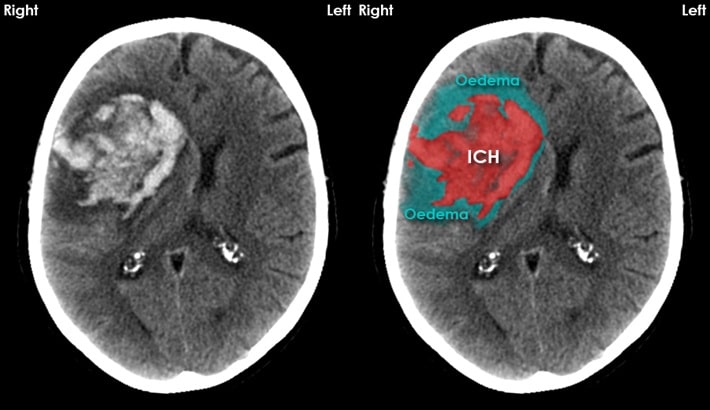

خونریزی مغزی یا هماتوم از خطرناکترین شرایط مغزی است که نیاز به تشخیص فوری و دقیق دارد. در چنین شرایطی، سی تی اسکن مغز بهعنوان سریعترین و قابلاعتمادترین روش تصویربرداری شناخته میشود. این روش میتواند حتی کوچکترین مقدار خونریزی را در عمق بافت مغز یا اطراف آن نشان دهد؛ همچنین پزشک را در انتخاب درمان فوری یاری کند.

نقش سی تی اسکن مغز در تشخیص خونریزی

سی تی اسکن مغز با استفاده از اشعه ایکس و فناوری کامپیوتری، تصاویر دقیق و چندبعدی از بافتهای داخلی مغز تهیه میکند. در این تصاویر، نواحی دچار خونریزی بهصورت روشنتر از بافت طبیعی مغز دیده میشوند. این ویژگی کمک میکند تا نوع و محل خونریزی مغزی بهسرعت مشخص شود.

انواع خونریزیهایی که در سی تی اسکن مغز قابل تشخیصاند:

سی تی اسکن مغز میتواند انواع مختلف هماتوم را از یکدیگر تفکیک کند.

هماتوم داخل مغزی:

در این نوع، خون درون بافت خود مغز جمع میشود. این حالت معمولاً بهدلیل فشار خون بالا یا پارگی عروق رخ میدهد.

مزیت سی تی اسکن مغز در شرایط اورژانسی

یکی از مزایای بزرگ سی تی اسکن مغز ، سرعت بالا و توانایی تشخیص فوری است. برخلاف امآرآی که زمان بیشتری میبرد، سی تی اسکن میتواند در کمتر از ده دقیقه انجام شود. این ویژگی در بیمارانی که دچار ضربه مغزی، سکته یا کاهش سطح هوشیاری هستند حیاتی است.